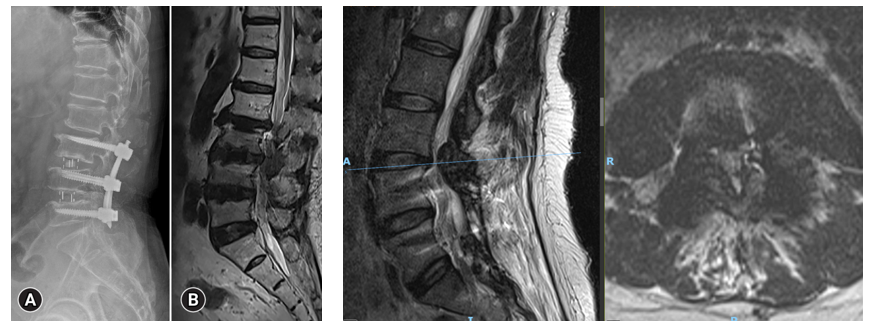

In recent years, there has been a steady and disquieting rise in the number of spinal fusion procedures being recommended and performed - many of which, upon rigorous examination, fall short of the stringent clinical thresholds that once defined the necessity of such an intervention.11,16 Fusion, while undeniably valuable and at times indispensable in cases of demonstrable mechanical instability (such as in spondylolisthesis with slippage, gross segmental hypermobility, or spinal deformity correction), is increasingly being applied in settings where the evidence of benefit is ambiguous or entirely absent (Figure 5).20–22

Figure 5 Typical lumbo-sacral arthrodesis.

• Heightened likelihood of revision surgery, particularly in multilevel constructs, elderly patients, or those with poor bone quality or pseudarthrosis (Figure 6).22,28

Figure 6 Two illustrative examples of “Adjacent Segment Disease”.